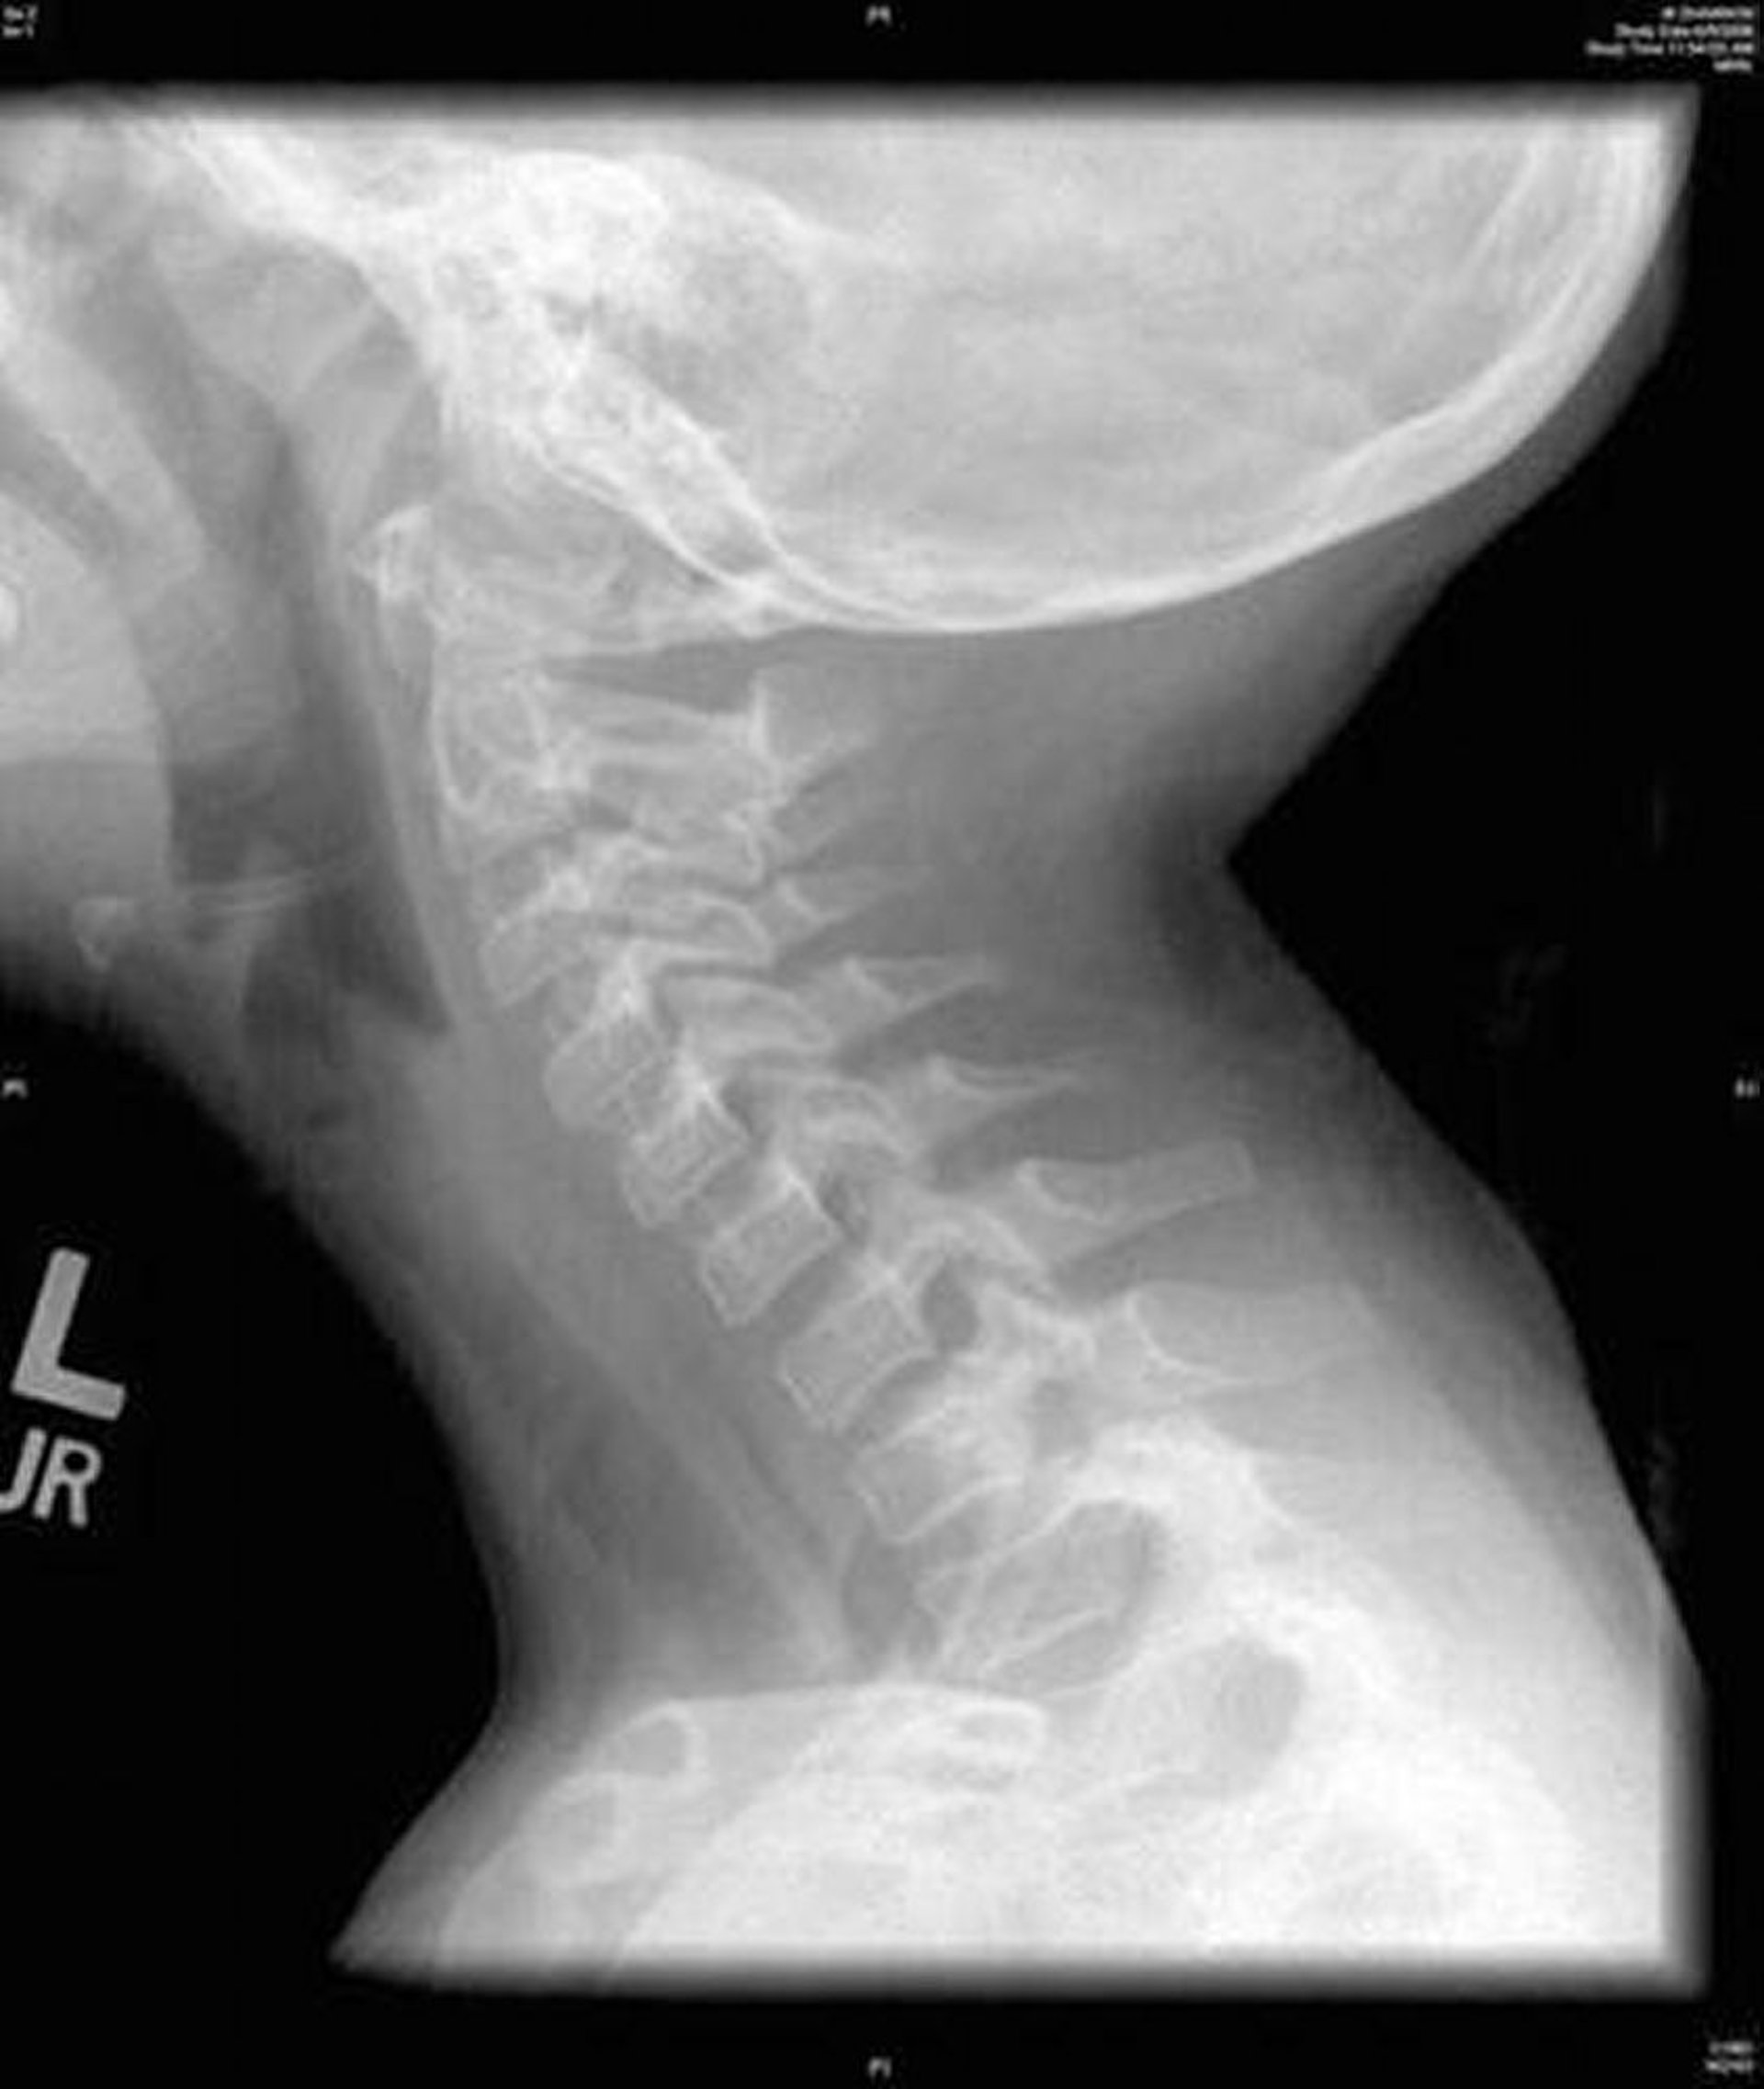

Questa immagine mostra una RX di profilo del collo che mostra un'irregolarità diffusa della trachea caratteristica della tracheite batterica.